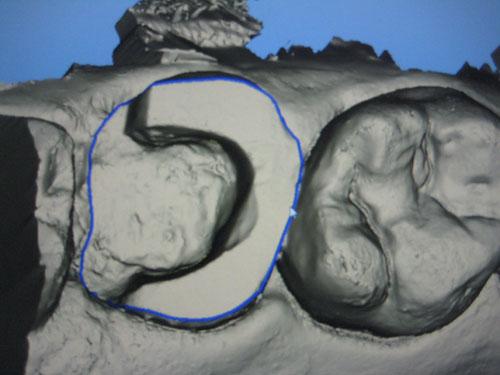

Le modèle virtuel va être fractionné

Tracé à l'écran des limites de la préparation